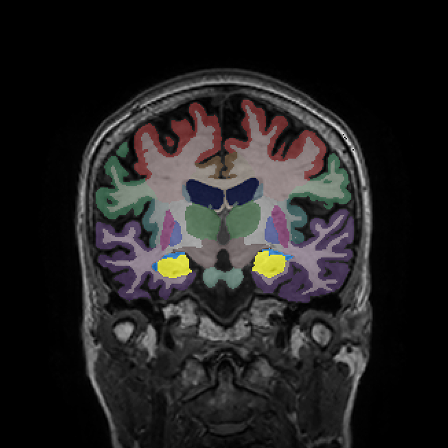

Longitudinal Tracking

Alzheimer's Disease Case Study 2

Retrospective brain volumetric analysis in a female patient diagnosed with Alzheimer’s disease at age 77 showed progressive brain atrophy over a 5-year period. The scans demonstrate temporal cortical atrophy with marked ex-vacuo enlargement of the lateral ventricles.

PATIENT

Female patient diagnosed with Alzheimer's Disease at Age 77

Analysis period

5 years

regions of interest

Temporal cortex

Hippocampus

Inferior lateral ventricles

Age 72

Age 74

Age 77

Lateral ventricle